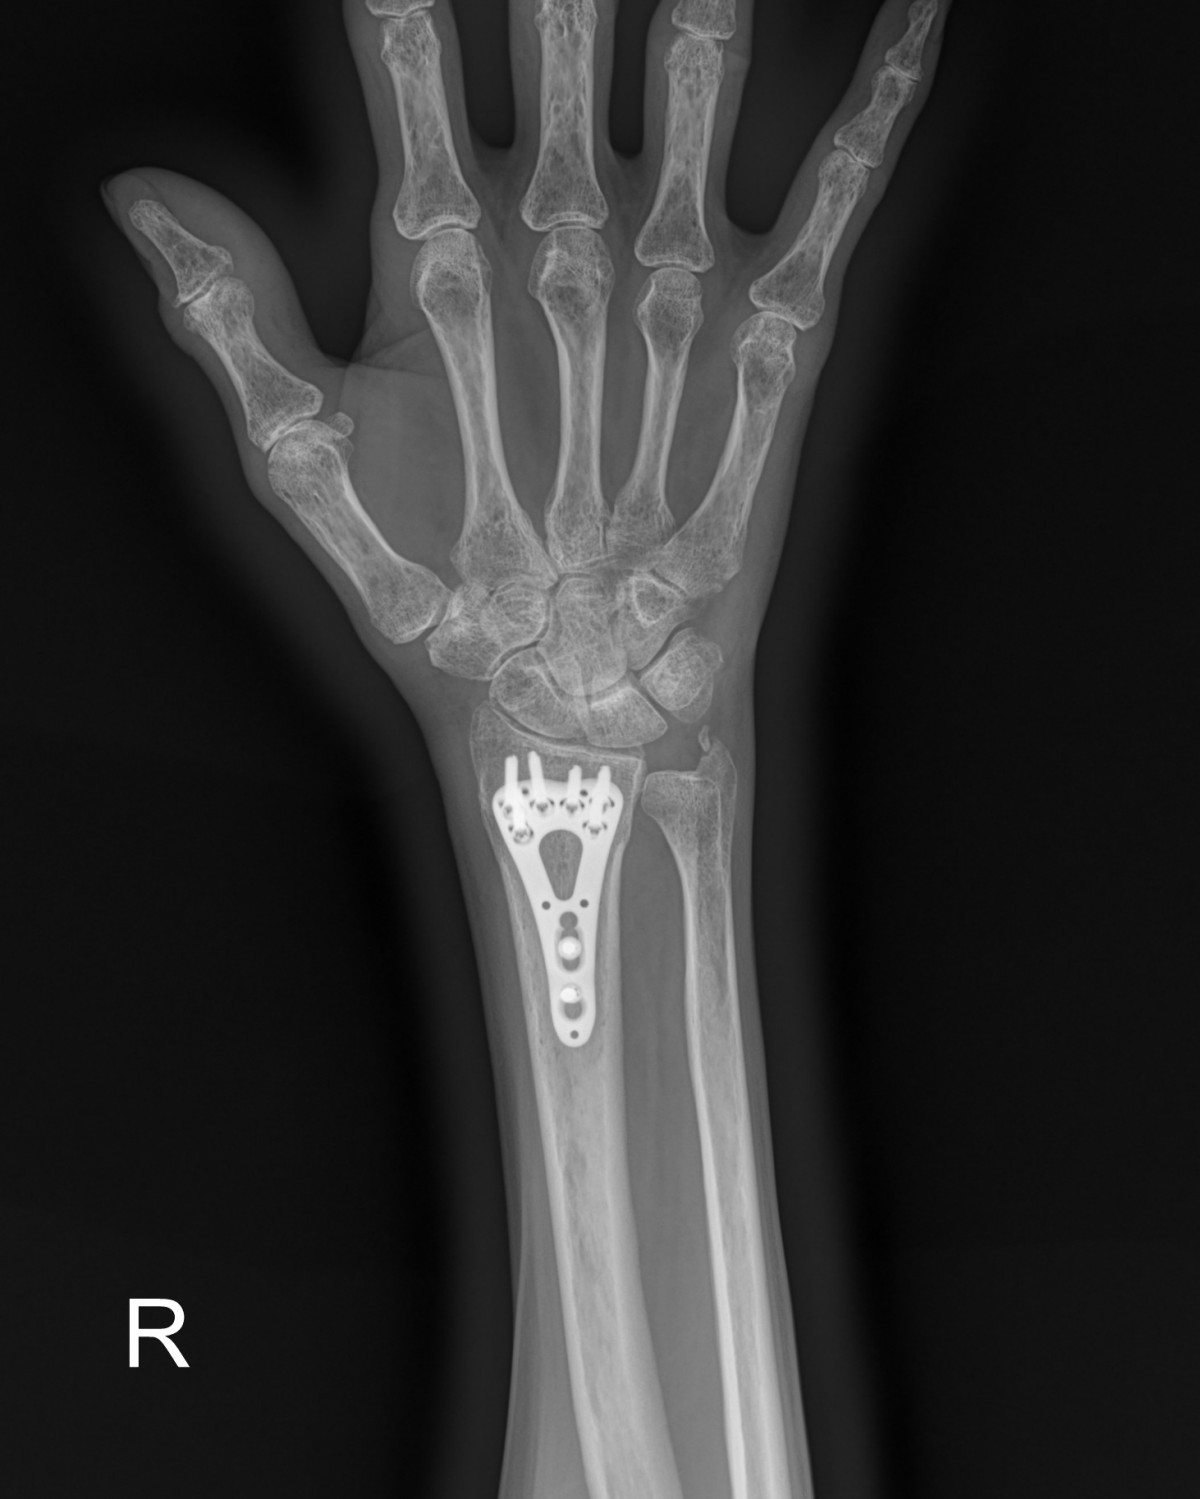

정지영원장님 손목 골절 수술 조효O 환자

dae765e4d9ac96aee867c9d6292d8784_1758008110_3788.jpg